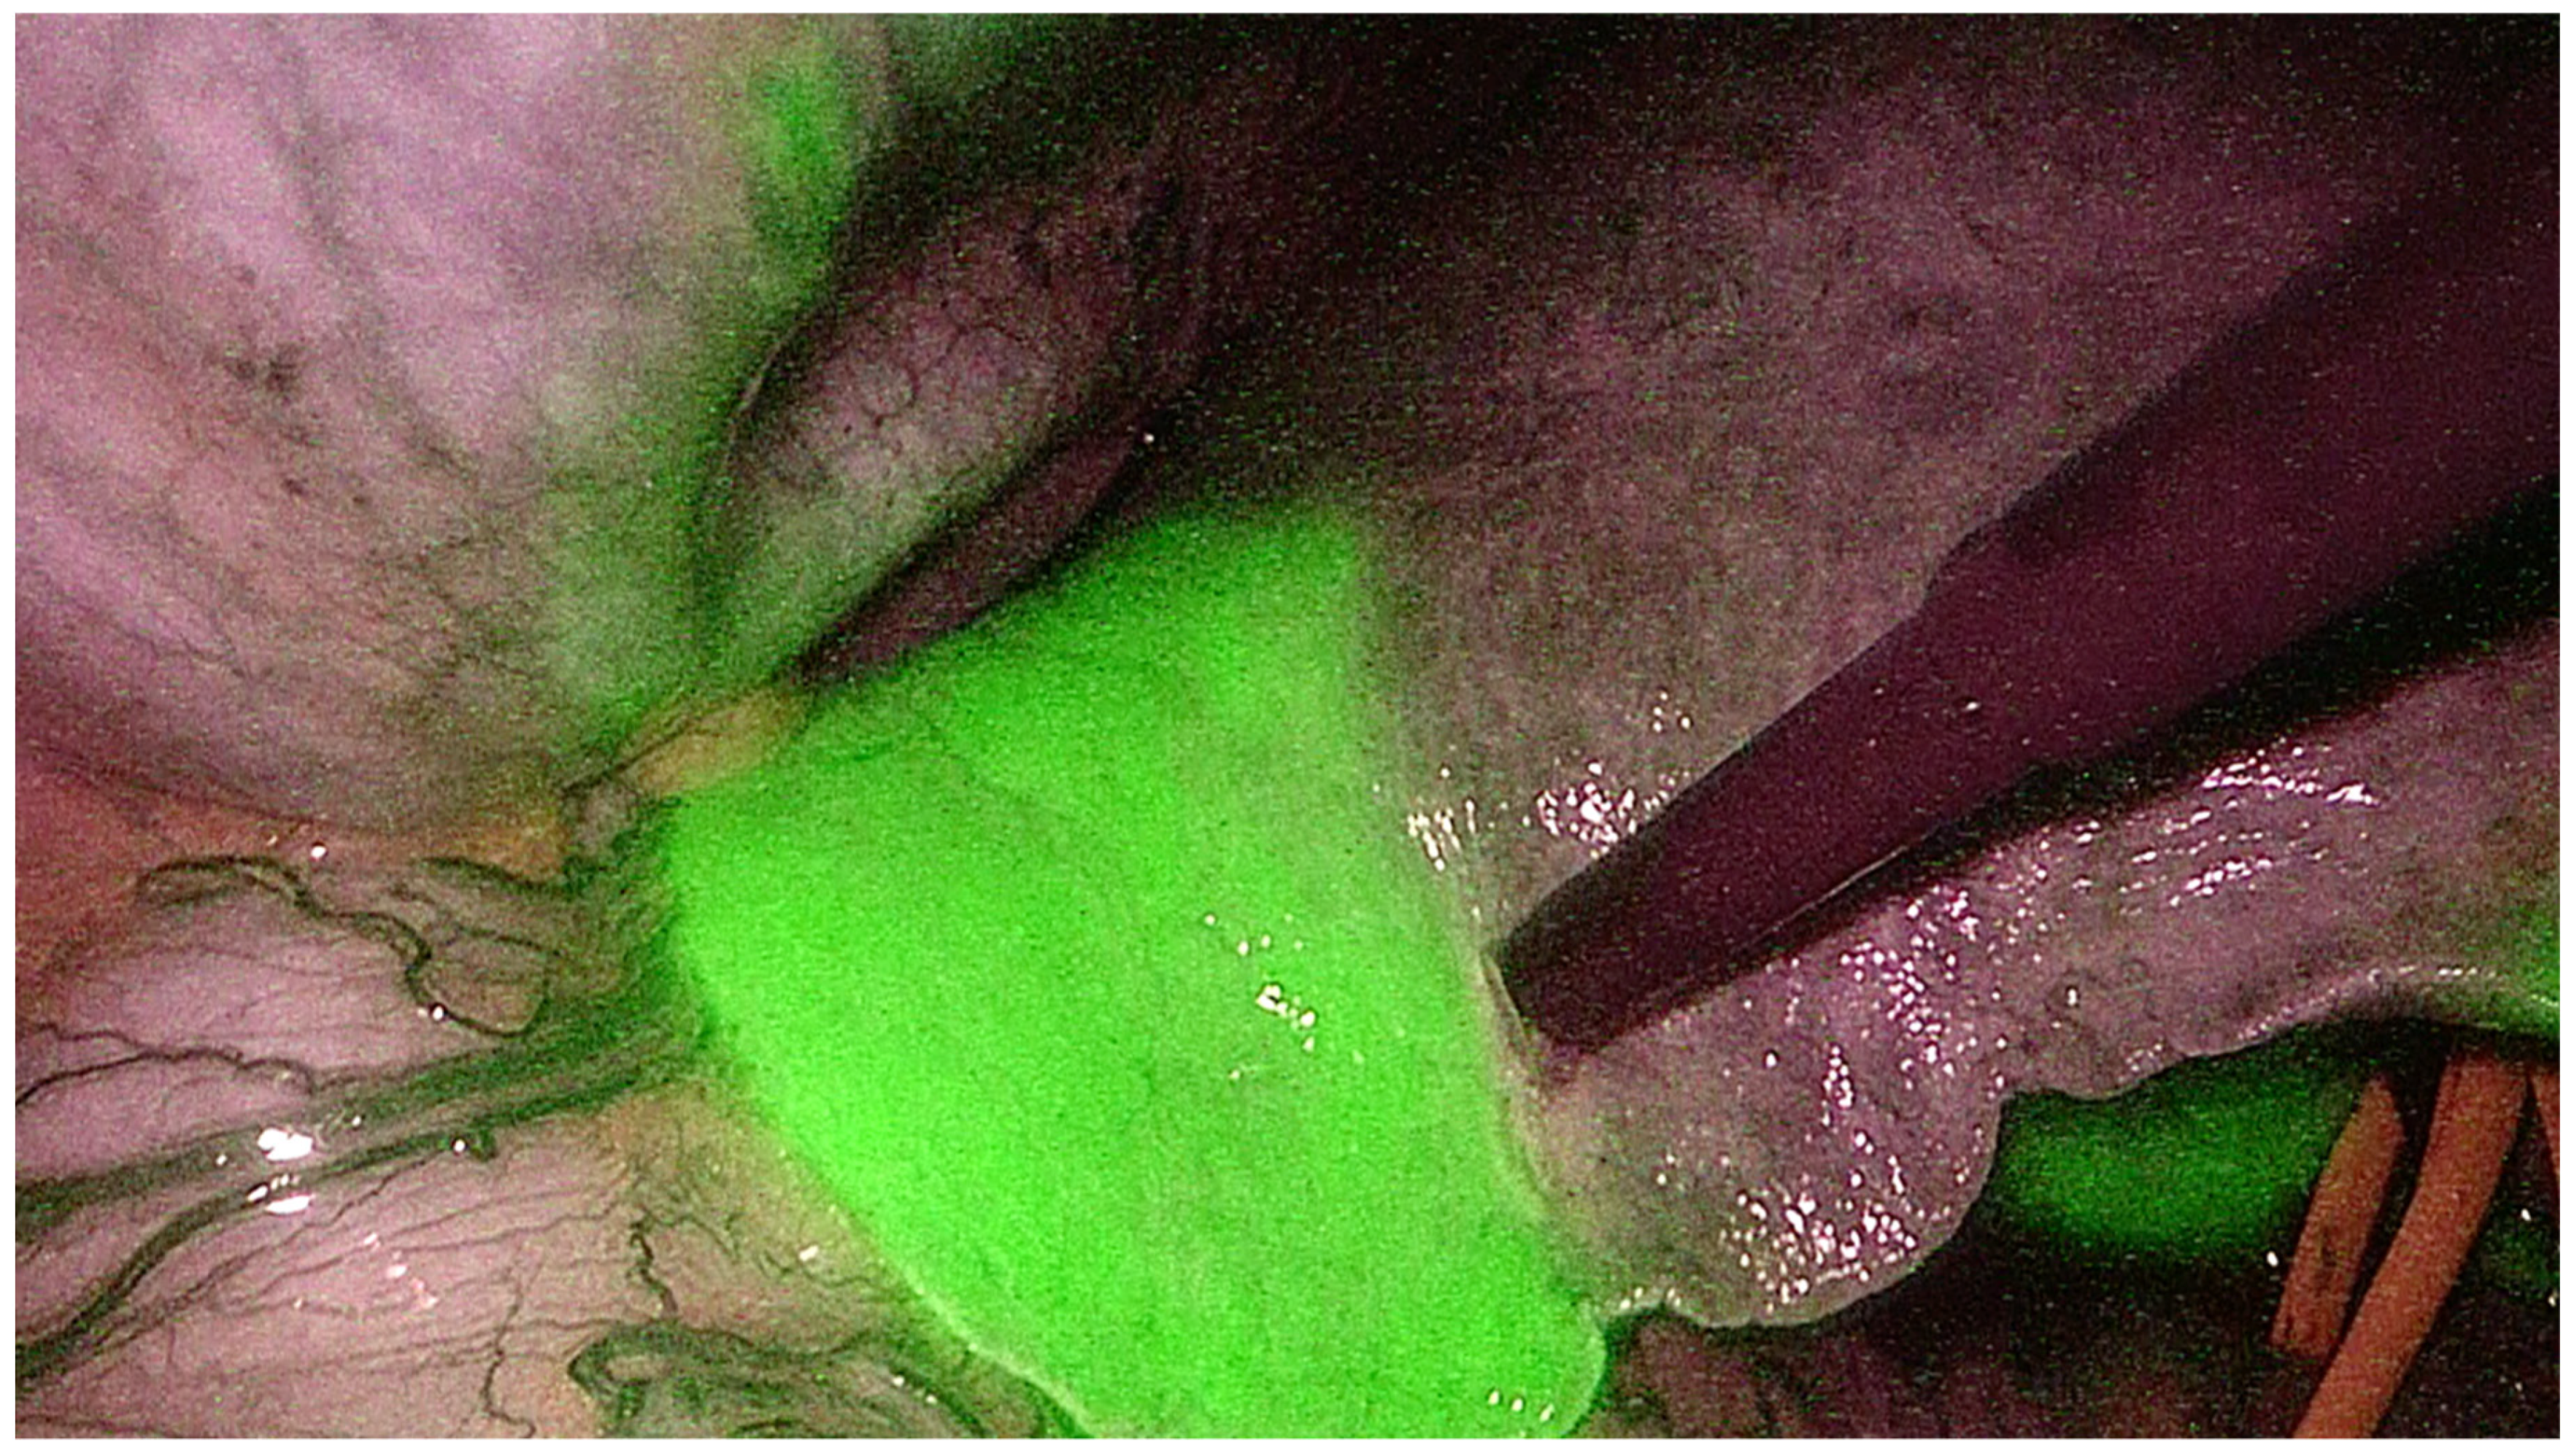

- Berardi, G.; Wakabayashi, G.; Igarashi, K.; Ozaki, T.; Toyota, N.; Tsuchiya, A.; Nishikawa, K. Full Laparoscopic Anatomical Segment 8 Resection for Hepatocellular Carcinoma Using the Glissonian Approach with Indocyanine Green Dye Fluorescence. Ann. Surg. Oncol. 2019, 26, 2577–2578. [Google Scholar] [CrossRef]

- Felli, E.; Ishizawa, T.; Cherkaoui, Z.; Diana, M.; Tripon, S.; Baumert, T.F.; Schuster, C.; Pessaux, P. Laparoscopic anatomical liver resection for malignancies using positive or negative staining technique with intraoperative indocyanine green-fluorescence imaging. HPB 2021, 23, 1647–1655. [Google Scholar] [CrossRef]

- Berardi, G.; Igarashi, K.; Li, C.J.; Ozaki, T.; Mishima, K.; Nakajima, K.; Honda, M.; Wakabayashi, G. Parenchymal Sparing Anatomical Liver Resections With Full Laparoscopic Approach: Description of Technique and Short-term Results. Ann. Surg. 2021, 273, 785–791. [Google Scholar] [CrossRef]